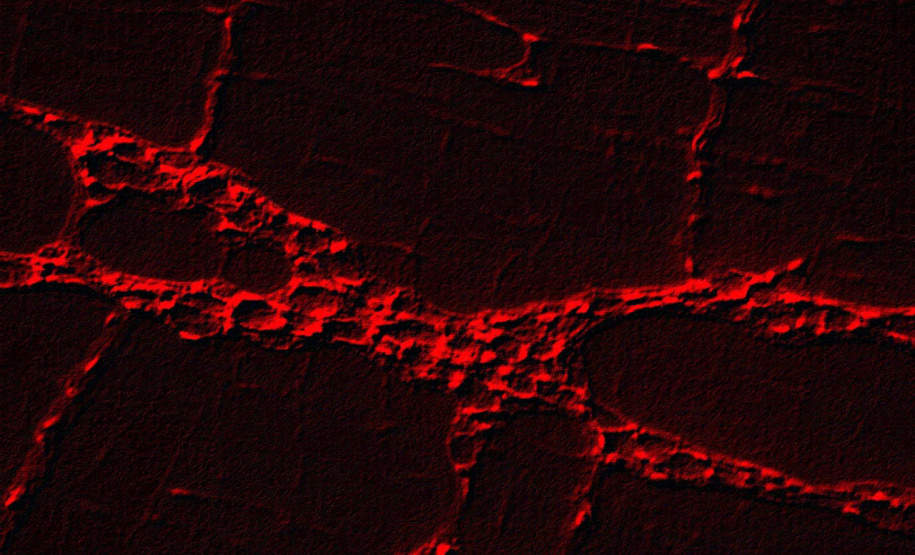

Pesquisadores da Universidade Estadual de Maringá (UEM) identificaram de forma automática a presença de três doenças crônico-degenerativas a partir do reconhecimento de padrões em imagens de células do sistema nervoso entérico de animais de laboratório. O estudo, considerado inédito, mostra que o método proposto é capaz de reconhecer corretamente a ocorrência das doenças com taxas de 89,3% para artrite reumatoide, 95,13% para diabetes e 98,45% para tumor de Walker (câncer).

PESQUISA – O orientador Gustavo Yandre Costa, professor no Departamento de Informática (DIN) e membro do Laboratório de Sistemas Interativos e Inteligentes da UEM, diz que a pesquisa partiu da hipótese de que poderia haver padrões ligados ao conteúdo visual dessas imagens, que seriam úteis para reconhecer essas doenças. “A partir disso, exploramos principalmente informações ligadas ao conteúdo de textura dessas imagens e utilizamos alguns algoritmos de classificação bastante conhecidos na literatura de inteligência artificial”, afirma.

Os pesquisadores avaliaram amostras de células de glia entérica. Foram avaliadas características obtidas com o método tradicional de engenharia e características aprendidas automaticamente com o uso de modelos profundos de aprendizagem. “Além da contribuição técnica para as análises pré-clínicas, visamos incentivar o desenvolvimento de técnicas e metodologias inéditas, capazes de apoiar a solução de problemas desafiadores existentes nas práticas laboratoriais”, afirma Gustavo.